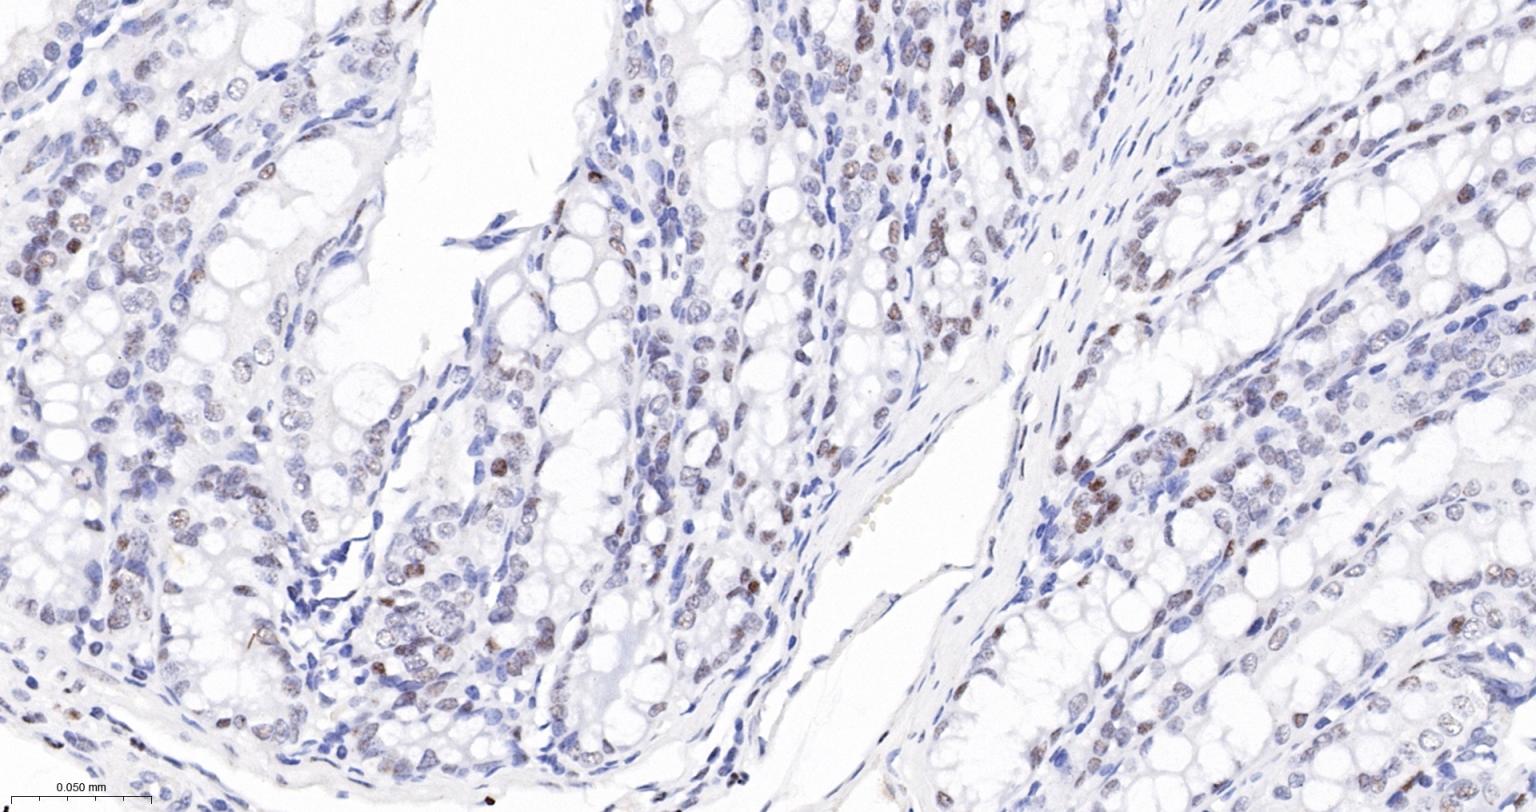

Paraformaldehyde-fixed, paraffin embedded Human Testicles; Antigen retrieval by boiling in sodium citrate buffer (pH6.0) for 15 min; The section was incubated with PB1 Monoclonal Antibody, Unconjugated (bsm-61815R) at 1:200 overnight at 4°C, followed by conjugation to the bs-0295G-HRP and DAB (C-0010) staining.